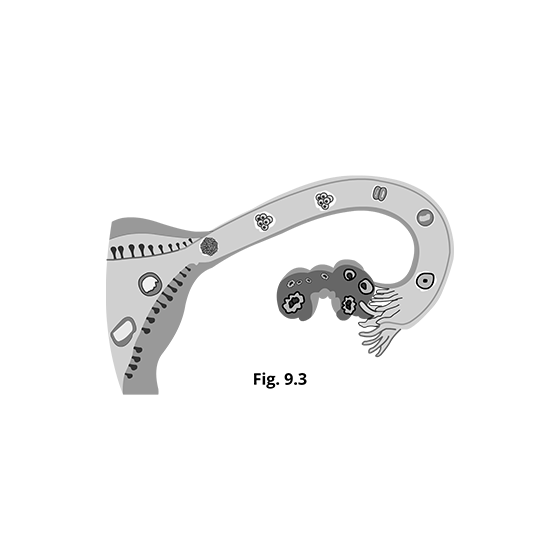

5. What do you mean by Menstrual Cycle?

After reaching adolescence, all females generate mature egg cells once a month during a process known as the menstrual cycle. An ovary releases a developed egg during this time, which goes to the uterus. If the egg is not fertilized in the uterus, the uterine lining sheds, and a new cycle begins. A menstrual cycle lasts 28 days on average, although it can be as short as 21 days or as long as 35 days in particular women. The endocrine system is in charge of the whole menstrual cycle, and the hormones involved include FSH, LH, estrogen, and progesterone. The pituitary gland produces FSH and LH hormones, whereas the ovaries generate estrogen and progesterone hormones. You can get all the details of Female Reproductive System Anatomy from Vedantu.